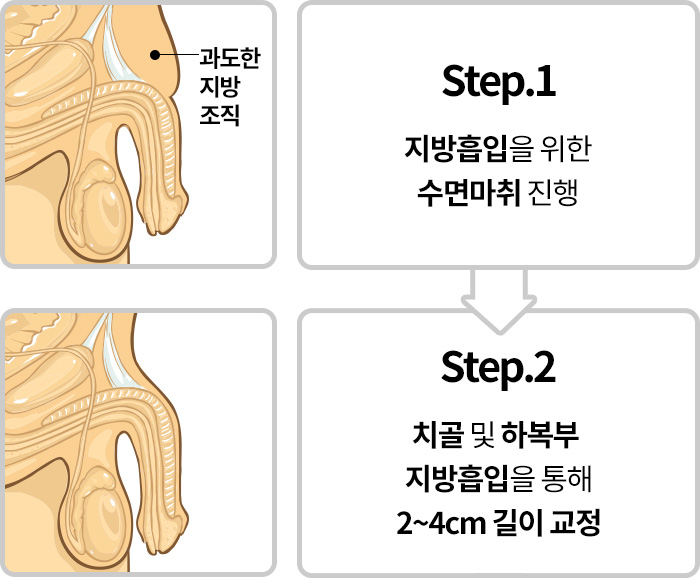

주된 원인이 하복부 및 치골주변의

과도한 지방조직에 의해 발생한 것인 만큼

지방흡입을 통해 길이연장의 효과를

기대해볼 수 있습니다